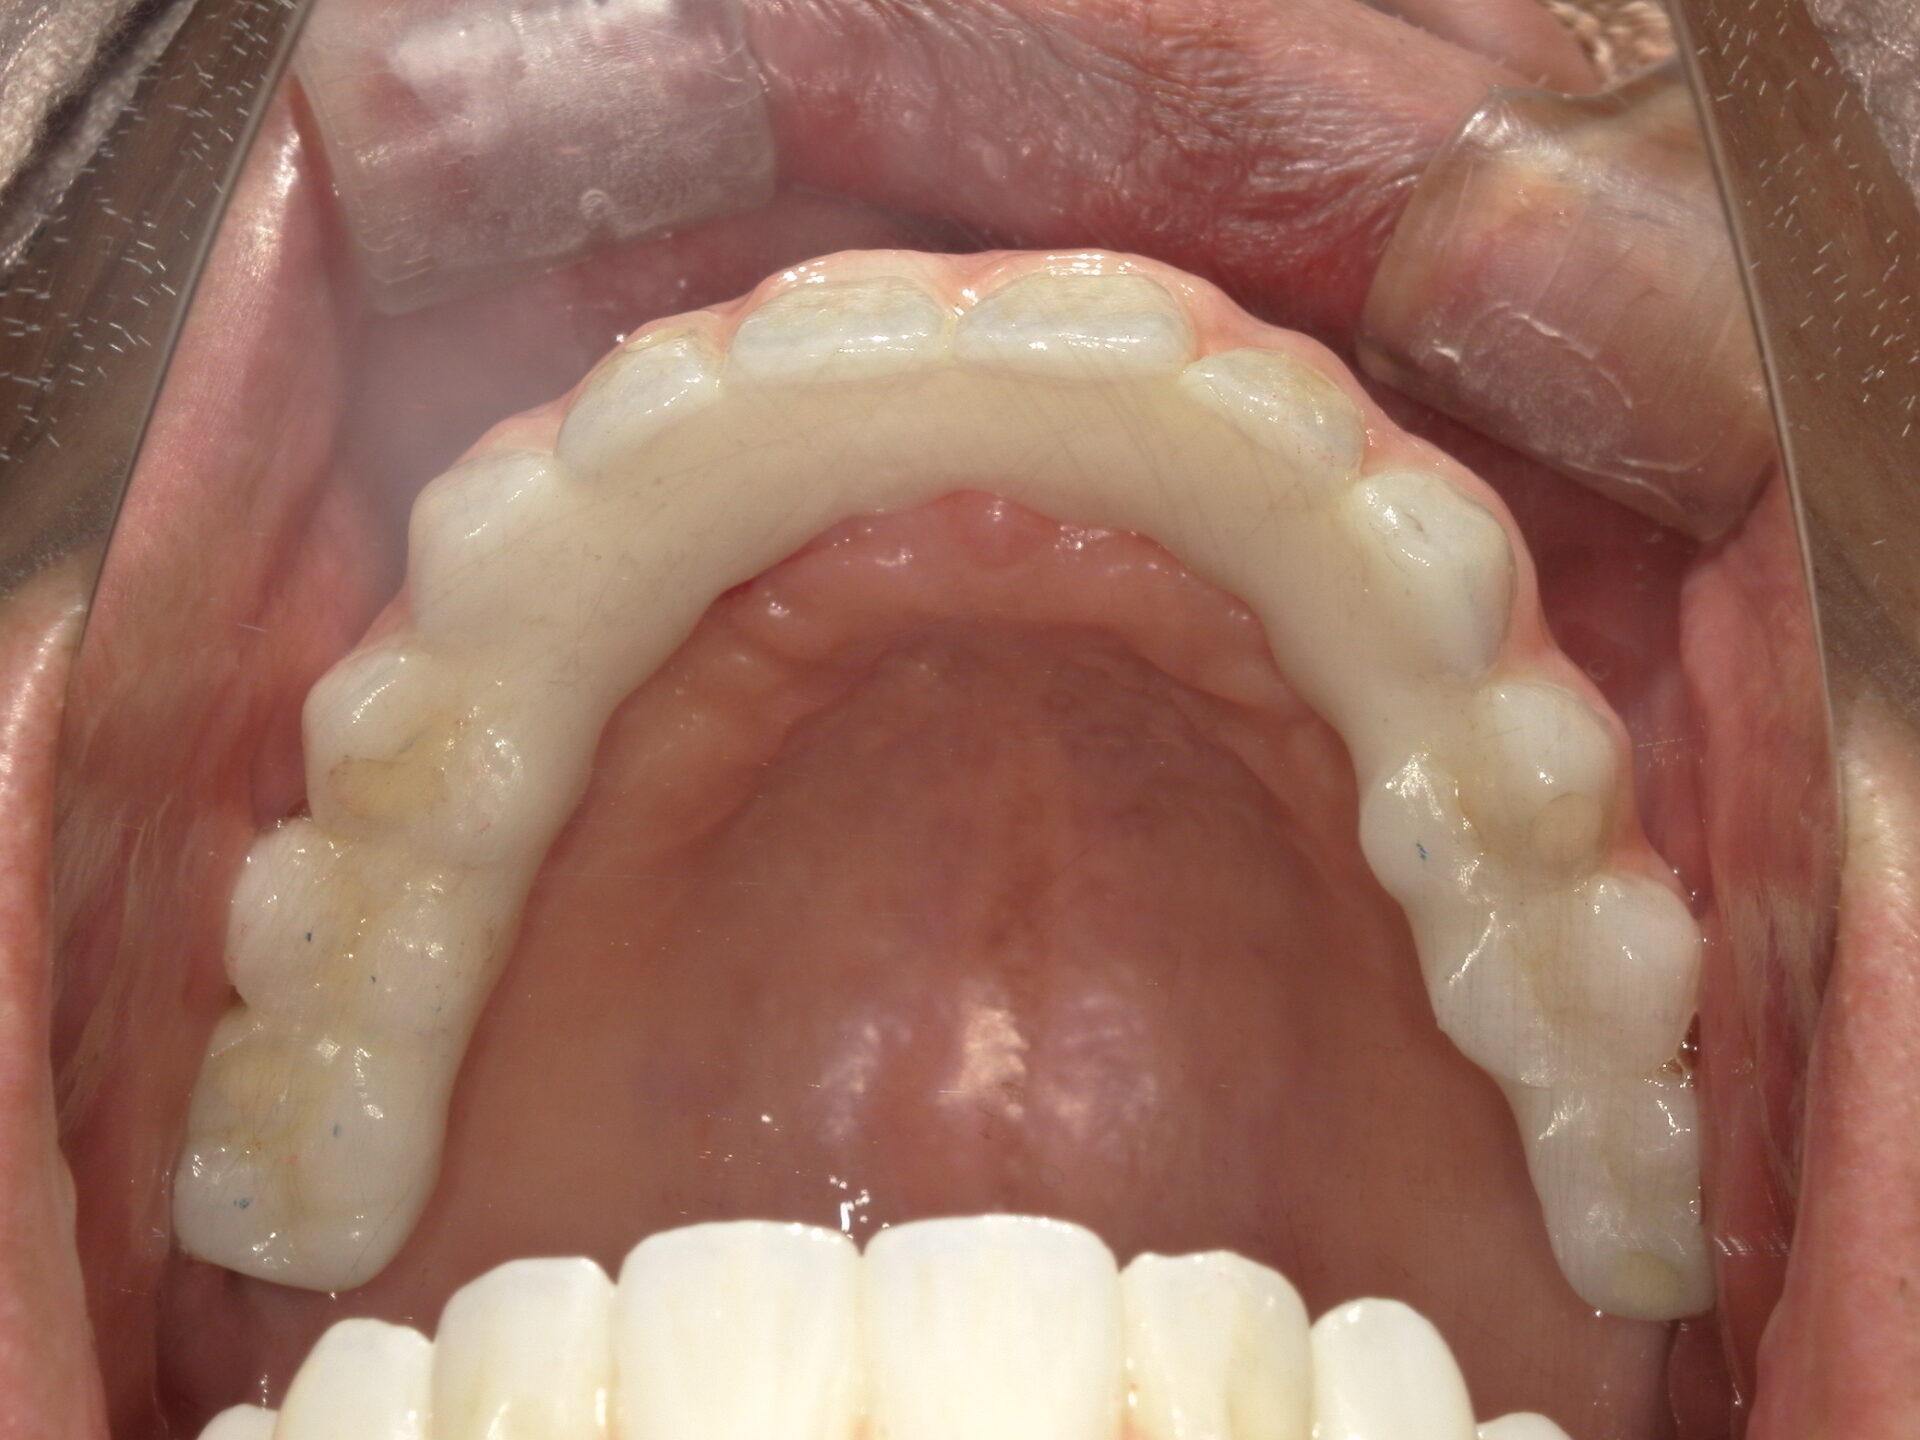

before

after

患者さんの年齢 50代 男性 症状 何も噛めない 治療内容 インプラント治療(オールオン4) 費用 費用900万(税抜) 治療期間・回数 治療期間2年・通院回数12回 メリット なんでも噛めるようになる 見た目が綺麗 デメリット・リスク 骨造成などで費用が増える場合がある - インプラント治療